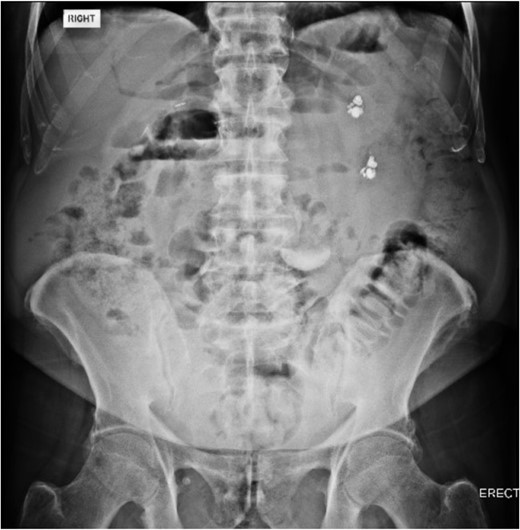

An 80 year old male presented to the emergency department after accidentally swallowing his hearing aids. On presentation he was pain free, hemodynamically stable, and had a soft abdomen. He had a background of type-2 diabetes, rheumatoid arthritis and diverticulitis. The hearing aids were powered by lithium battery. X-ray found two foreign bodies in the left upper abdomen (Fig. 1). After assessment in the emergency department, he returned home to await their natural passage. One hearing aid was found in his stools the following day, but he represented three weeks later as the second hearing aid remained unaccounted for. He underwent repeat abdominal x-ray and CT, which found the hearing aid retained within a presumed distal duodenal diverticulum (Figs 2 and 3). He was booked a push enteroscopy the following day.

Abdominal X-ray identifying two hearing aids on day of initial presentation.